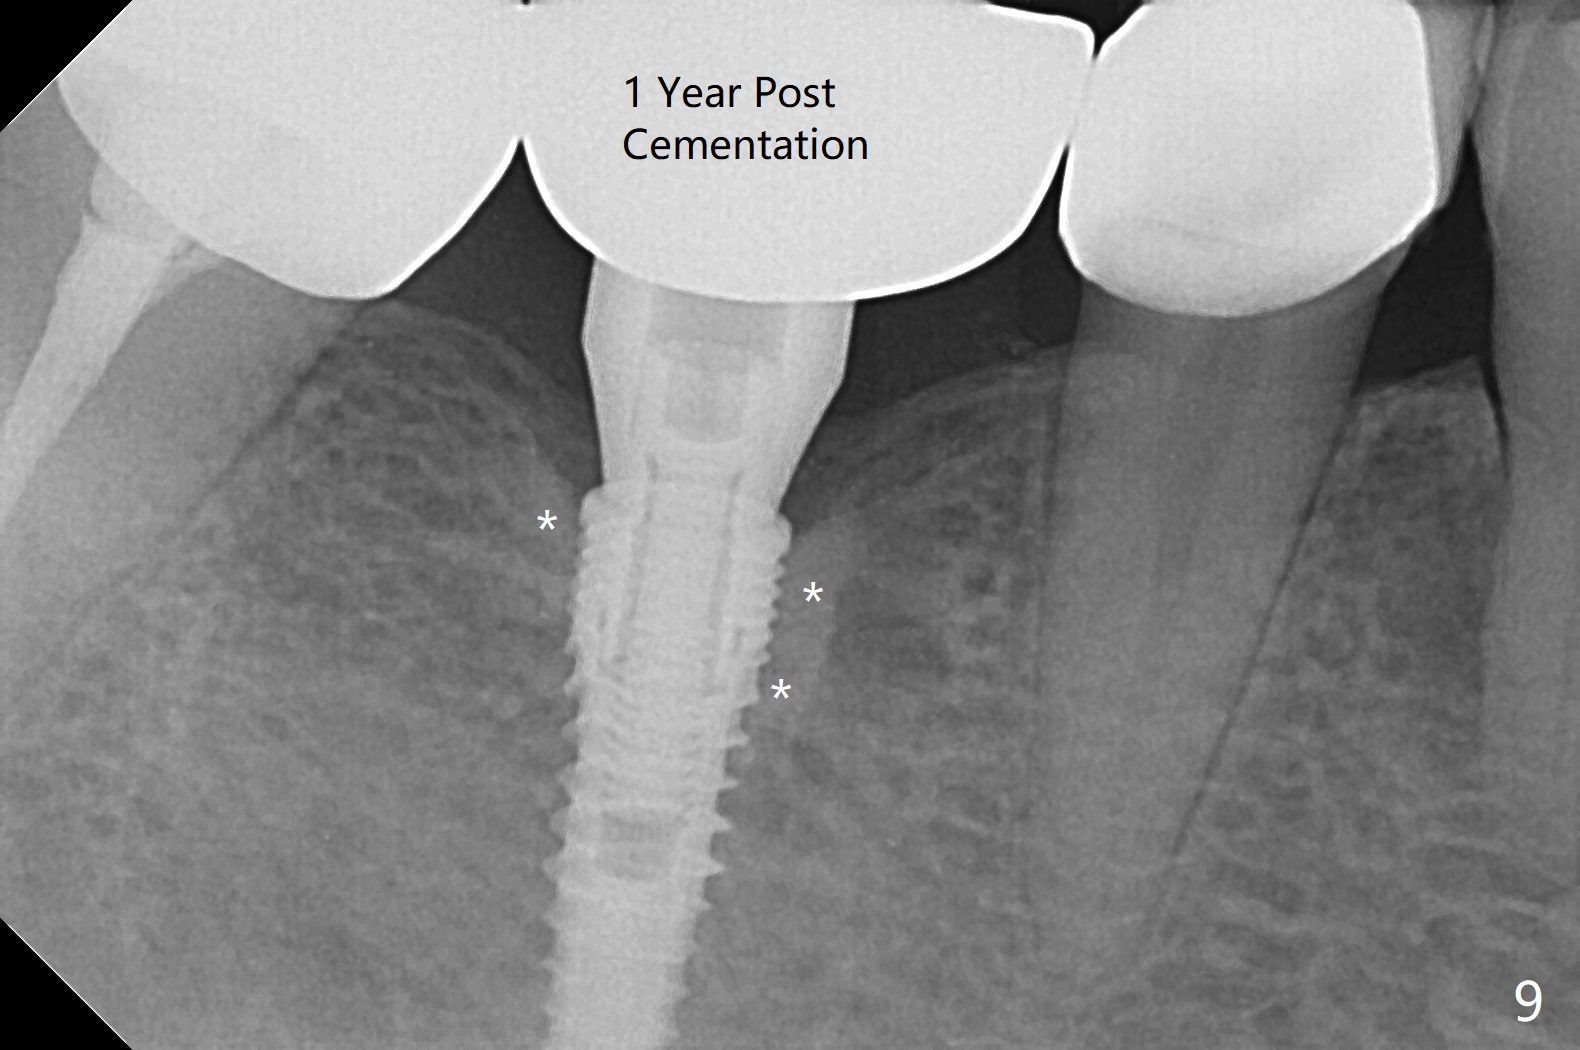

The apparently narrow ridge at #30 before bridge sectioning (Fig.1) is confirmed with incision (Fig.2). Following ridge reduction, osteotomy is initiated with 2 mm pilot drill (Fig.3). When a 3.8x12 mm SM narrow implant is placed with 40 Ncm, there is 1-2 mm cortical bone buccolingually (Fig.4,5). The thick cortices do not seem to be easy to be bent, i.e., expanded. RCT is finished at #31 one month post implant placement (Fig.6,7), the flattened ridge appears to have started to undergo remodeling. Ridge reduction makes it possible for the implant to remain subcrestal postop (Fig.4). The bone surrounding the implant may reduce the likelihood of implant fracture. The crowns at #30 and 31will be fabricated together with light occlusion at #30. In fact the splinted provisional dislodges. There appears dense bone formation 3 months postop (Fig.8 *). The drawback of using a SM narrow implant is that a narrow abutment has to be used (4.8x4(4.5) mm). The implant crown is dislodged immediately after the patient finishes lunch. Following recementation, the occlusion is reduced. In fact, UF or IBS has no such drawback: the implant could be small, but the abutment could be large. One year post cementation, the crown at #31 needs recementation (Fig.9); the bone density next to the coronal implant increases (*).